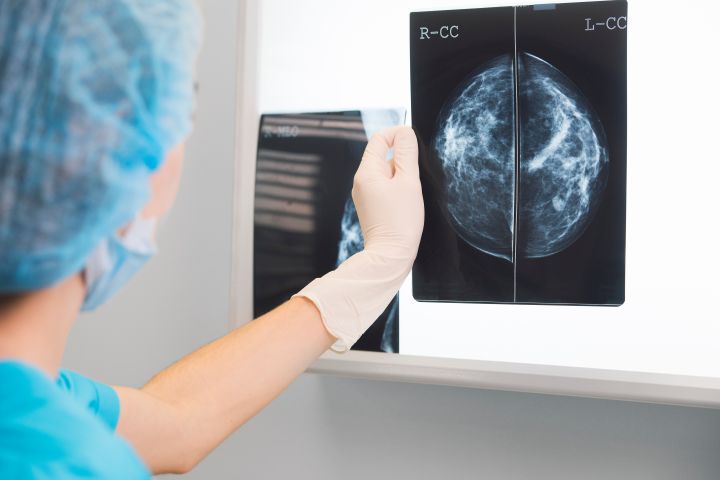

There is no correlation between breast size and cancer. In terms of examination, large breasts may be harder to examine even with exams and mammograms. All women should get screened. (Source: Health.com)

Research has shown that women with breast implants are not at risk of getting breast cancer but that taking mammograms may be a little harder for them. (Source: Health.com)

9. Myth: Getting annual mammograms exposes you to radiation that can cause breast cancer.

Radiation is used during mammograms, but the amount is very little and poses no risk. Mammograms are good at finding lumps that couldn’t be found during self-examinations. Women at the age of 40 and above should have a scheduled mammogram every one to two years. (Source: Health.com)

12. Myth: If your mammography report is negative, there is nothing to worry about.

Mammograms can’t detect 10-20 percent of breast cancer. Clinical breast exams and even self-breast examinations are important. (Source: Health.com)